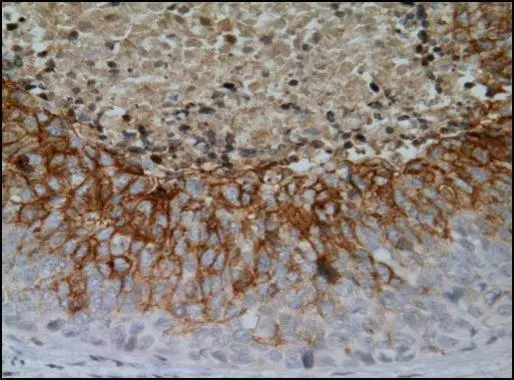

Anti-Carbonic Anhydrase IX antibody [GT12] used in IHC (Paraffin sections) (IHC-P). GTX70020

GTX70020 IHC-P Image

Carbonic Anhydrase IX antibody [GT12] detects Carbonic Anhydrase IX protein at cell membrane by immunohistochemical analysis.

Sample: Paraffin-embedded human cervical carcinoma.

Carbonic Anhydrase IX stained by Carbonic Anhydrase IX antibody [GT12] (GTX70020) diluted at 1:500.

Antigen Retrieval: Citrate buffer, pH 6.0, 15 min